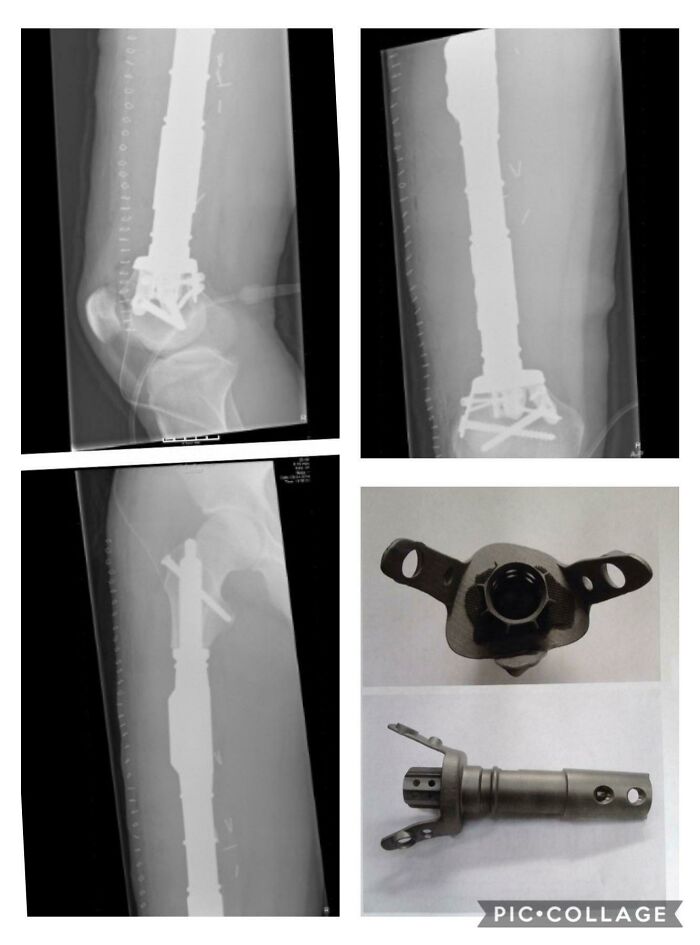

#59 According To My Doctor I Was The First Person In The World To Receive A 3D Printed Bone In 2014. Without It, I Would Have Lost My Knee.

Image credits: Sverre124